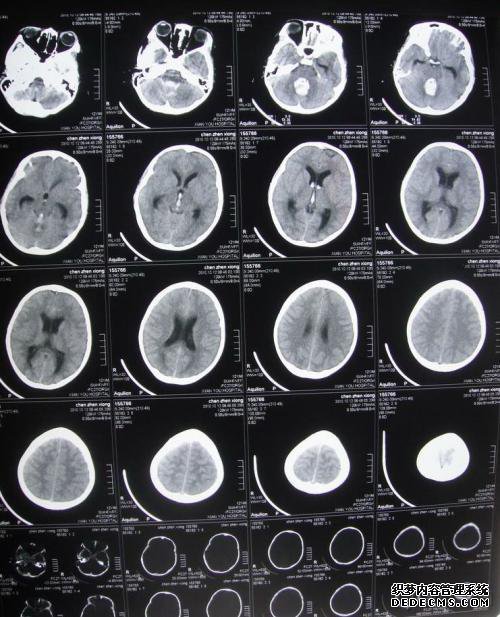

“脑子里有多少钱”这个问题使很多人感到担忧。毕竟,金钱对我们来说非常重要。没有钱真的很难。向所有人展示大脑并不昂贵,但大约需要200-300元人民币,具体费用将受到医院,位置,设备等因素的影响。

对脑ct的成本有一些了解,脑ct的价格不是很高,大多数人都能负担得起,因此,当您发现异常的脑部疾病,例如经常出现脑痛的人突然,无法解释的疾病,乳化呕吐,脑部ct奔跑,及时找到病因并控制病情,需要长时间的耳鸣,视力模糊,突然模糊。

但是,ct是放射线,没有特殊情况,因为会对人体造成一定的损害,因此无需经常进行验证,但是如果偶尔与光接触,则此问题并不重要。